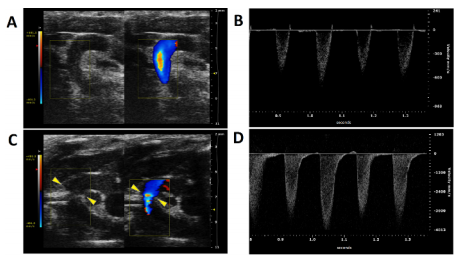

Fig.2.Color and Pulsed-wave Doppler Ultrasound Imaging from the Aortic Arch of Ligated and Non-ligated Mice. A) Color Doppler imaging of the aortic arch of a non-ligated mouse. The two carotid arteries are clearly visible, as well as the lack of a constriction between them. B) Aortic peak flow velocity of a non-ligated mouse. C) Color Doppler imaging of the aortic arch of a ligated mouse. The constriction between the two carotid arteries on the aortic arch is visible (yellow arrowheads). D) Peak flow velocity at the constriction site.